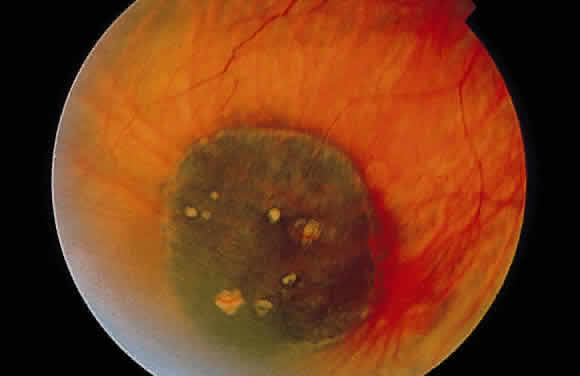

Retinochoroidal colobomas are glistening white or yellow defects with distinct borders that occur inferior or inferonasal to the optic disc (Fig. 12). They may extend up to and involve the optic disc (Fig. 13), or they may be seen as isolated chorioretinal defects. The margins of the coloboma often are pigmented, and the defect is filled with abnormal retinal tissue. Anteriorly, the defect can extend as far as the iris and produce an inferonasal gap (Fig. 14). These anomalies may occur in otherwise normal persons or in association with chromosomal abnormalities or multisystem diseases, such as trisomy 13, the Aicardi syndrome, Goldenhar's syndrome, and the CHARGE association.148,152,153 Occasionally, autosomal dominant or recessive inheritance patterns are found, but often none are evident.152 In families with autosomal dominant inheritance, variable expression of the genetic trait makes genetic counseling difficult.154

Fig. 12. Isolated retinochoroidal coloboma with pigmented borders positioned inferior to the nerve head. The sclera is visible through the thinned, overlying retinal tissue.

Embryologically, retinochoroidal colobomas arise from failure of the embryonic fissure to close. Consequently, the inner and outer layers of the optic cup are abnormal in this region. The inner layer (sensory retina) usually is present as a membrane of undifferentiated retina that may have blood vessels going through it (see Figs. 12 and 13). The outer layer (RPE) is absent, and since the choroid is dependent on the RPE for its development, it also is lacking.